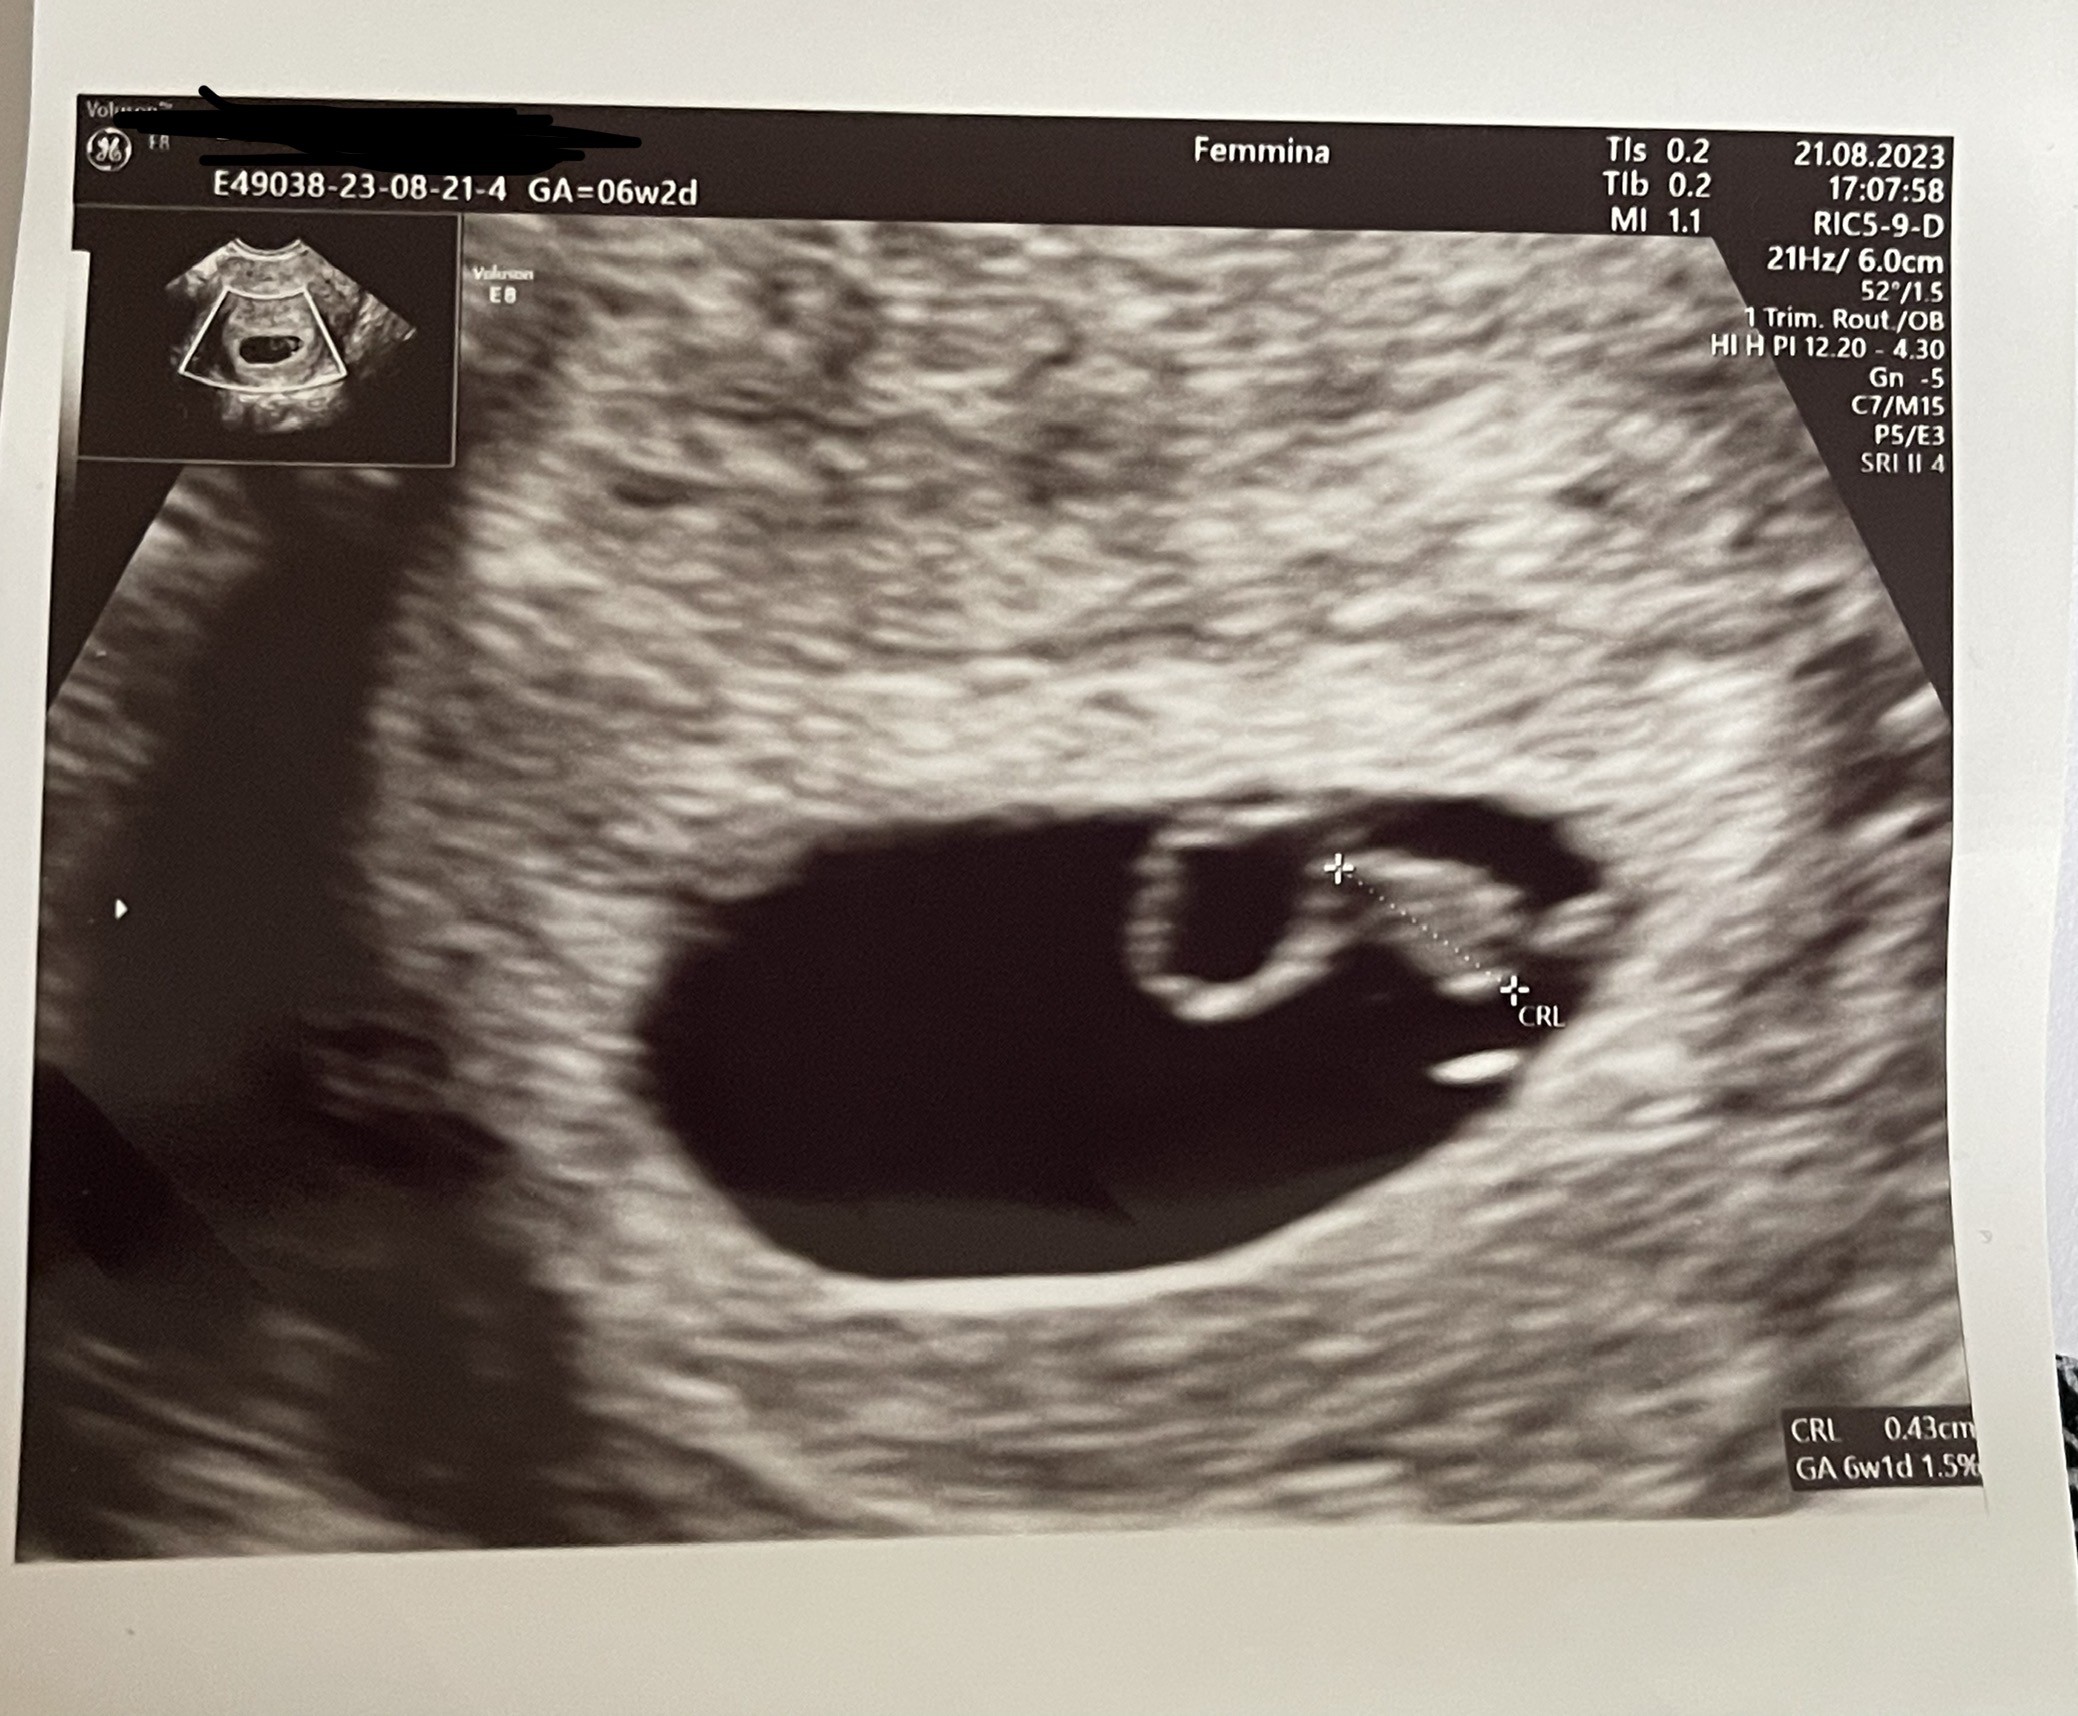

ja tez już po wizycie 😊 termin na 13 kwietnia, wszystko jest w porządku, widziałam pulsujące serduszko

Załączniki

• IMG_1046.jpeg

IMG_1046.jpeg

580,7 KB · Wyświetleń: 120